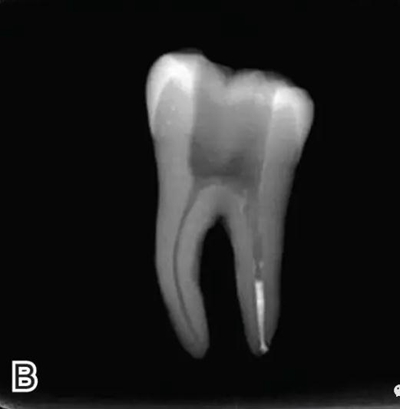

8、熱牙膠根中上段的充填

在完成根尖段的充填后,使用熱塑牙膠注射儀對根管中上段進(jìn)行分層充填,一般分2~3次完成充填,每次充填均使用相應(yīng)直徑大小的垂直加壓器進(jìn)行加壓。拍片確認(rèn)充填效果(圖8)。

圖8 熱牙膠根中上段的充填,A、B.注射儀注射中段熱牙膠

C、D.垂直加壓器加壓 E、F.注射儀繼續(xù)注射上段熱牙膠

G、H.垂直加壓器加壓 I、J.完成根中上段的充填